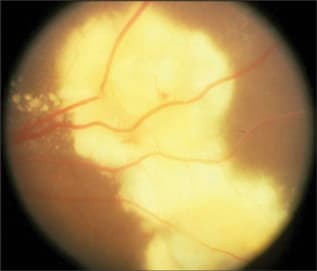

Toxocara endophthalmitis may present in 3 classic forms: chronic endophthalmitis, posterior pole "granuloma," and peripheral inflammatory mass. There is no external inflammation in the chronic endophthalmitis form.120 An acute inflammation phase with associated anterior granulomatous response and yellowish-white infiltrates in the vitreous and retina may either subside or be followed by fibrocellular membrane development deep within the vitreous.121 Prognosis depends on the extent of intravitreous organization. The posterior pole granuloma form usually presents with strabismus. The vitreous is hazy with an ill-defined posterior pole mass that becomes well-defined as a gray granulomatous mass as the initial inflammation subsides (Figure 5). Visual prognosis is usually good with stable vision, although there is usually already some loss of central vision by the time of diagnosis.122 The peripheral inflammatory mass form may be preceded by acute diffuse endophthalmitis. As the inflammation subsides, a peripheral dense white mass becomes apparent, which is either diffuse or spherical.123 Prognosis is relatively good, although surgical treatment, such as scleral buckling and vitrectomy, may be required if there are associated intraretinal bands and resultant retinal detachment.124-126

Figure 5. Toxocara canis retinitis.